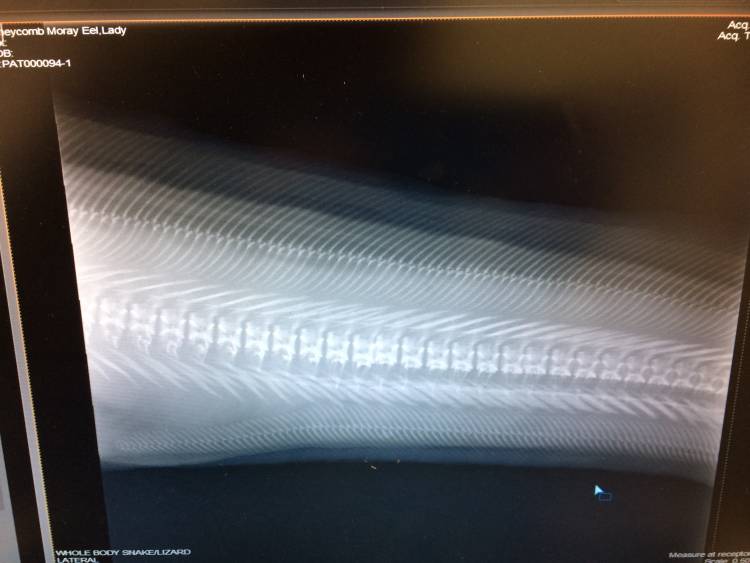

Further X-rays were taken of Lady’s abdominal area and spine. Blood was also drawn – this can be quite a challenge in eels as it is not easy to pierce the tough skin with a needle. The blood was sent to a pathology laboratory for testing.

An X-ray of Lady's spine. Photo by Helen Lockhart